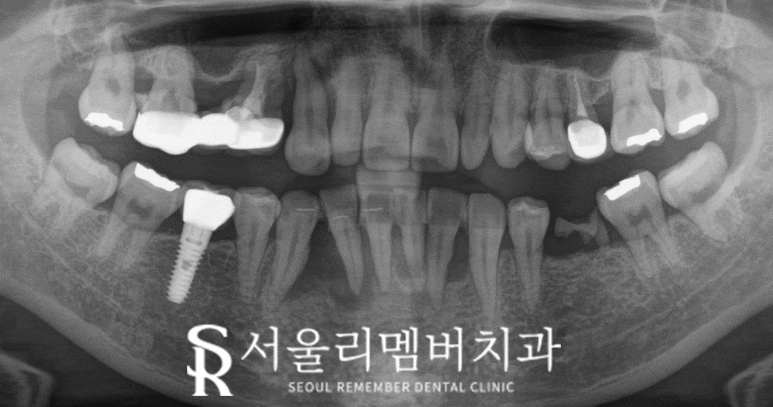

엑스레이 촬영 결과

아래 앞니 5개의 주변 치은이

심하게 퇴축되어 있었고,

뿌리가 거의 다 드러나 있었습니다.

다음과 같이 상황을 설명드렸습니다.

“현재 아래 앞니 다섯 개가 잇몸뼈에서

지지를 제대로 받지 못하고 있어서,

이 상태로는 유지하기 어려울 것 같습니다.

빠지기 전에 발치를 하고 임플란트 를

하는 방법이 적합한 방법일 것 같습니다.”

저는 43, 42, 41, 31, 32번을 발치한 후

43번과 32번 부위에 임플란트를 심고,

그 위에 5번 브릿지를 올려 저작 기능을 회복하며

자연스러운 미소를 찾을 수 있도록

진행하기로 계획 했습니다.